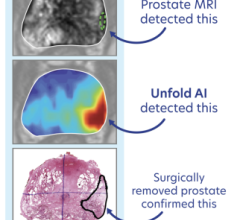

In scans of a 62-yr-old man with Gleason 4+3 PCa treated with radical prostatectomy, with rising PSA level (1.32) and PSA doubling time of 3.7 months, 64CuCl2-PET/CT images revealed 2 positive small left iliac lymph nodes (A,C), whereas 18F-Choline PET/CT (B,D) was negative (arrows). Image courtesy of A Piccardo et al., Galliera Hospital, Genoa, Italy.

An Italian study featured in the March issue of The Journal of Nuclear Medicine demonstrates that a novel nuclear medicine imaging agent targeting copper accumulation in tumors can detect prostate cancer recurrence early in patients with biochemical relapse (rising prostate-specific antigen [PSA] level).

Copper tends to be more concentrated in tumors, making it a good imaging biomarker. For this study of 50 patients, researchers conducted PET/CT scans comparing the new imaging agent, copper-64 chloride (64CuCl2), with fluorine-18-choline (18F-Choline). Multiparametric magnetic resonance imaging (mpMRI) was also conducted. In addition to calculating the detection rate of each imaging modality, the biodistribution, kinetics of the lesions and radiation dosimetry of 64CuCl2 were evaluated.

"This is the first time this novel agent has been compared with 18F-Choline-PET/CT in a considerable number of prostate cancer patients with biochemical relapse," explained Arnoldo Piccardo, of E.O. Ospedali Galliera in Genoa, Italy. He points out, "Early detection of prostate cancer relapse may improve the clinical management of patients, for example implementing early salvage radiotherapy."

The effective dose of 64CuCl2 was determined to be 5.7 mSv, similar to those of other established PET tracers (although higher than for 18F-Choline, which is 4 mSv). Unlike 18F-Choline, 64CuCl2 is neither accumulated in, nor excreted from, the urinary tract (main uptake is in the liver); this allows for thorough pelvic assessment, increasing the possibility of identifying small lesions close to the bladder. No adverse reactions were observed after the injection of 64CuCl2, and results show that 64CuCl2-PET/CT has a higher detection rate than 18F-Choline-PET/CT in patients with low levels of PSA (<1 ng/ml).

"This study determined that the biodistribution of 64CuCl2 is more suitable than that of 18F-Choline for exploring the pelvis and prostatic bed," said Piccardo. "In patients with biochemical relapse and a low PSA level, 64CuCl2-PET/CT shows a significantly higher detection rate than 18F-Choline-PET/CT." He reports, "Larger trials with this PET tracer are expected to further define its capabilities and role in the management of prostate cancer."